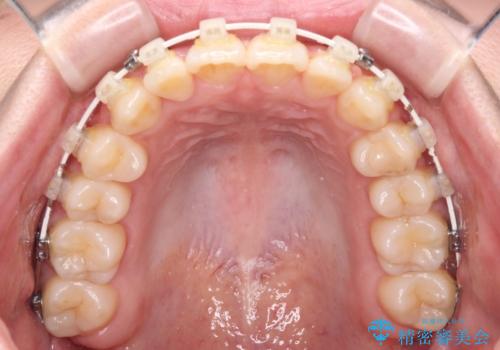

前歯のクロスバイト 目立たないワイヤー装置で速やかに矯正治療

- 前歯のクロスバイトを気にして来院された患者様です。

治療方法としては、マウスピース矯正(インビザライン)でもワイヤー矯正でも、何でも対応可能ですが、自己管理の煩わしさがなく、治療期間の目処を立てやすい表側のワイヤー矯正にて治療を行うこととしました。

治療前にお伝えした治療期間は1~1年半でして、1年4か月の期間で終えることができました。